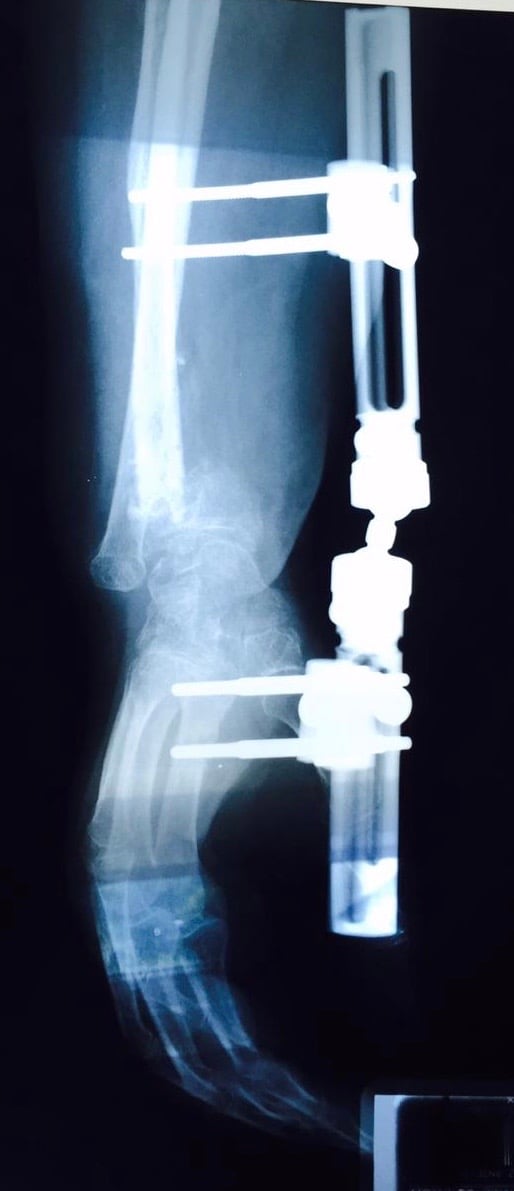

• Secuelas de: fracturas, fisuras, luxaciones, esguinces, tendinitis, tendinosis,  y desgarres musculares.

• Post operados de: Columna, Hombro, Codo, Muñeca, Mano y Dedos, Cadera, Rodilla, Tobillo y Pie

• Amputaciones (manejo de muñón, rehabilitación pre-protésica y protésica funcional)